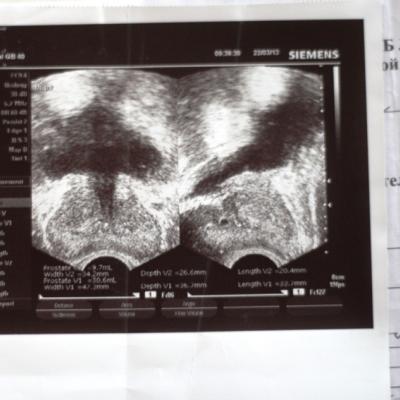

26.04.2013 г. меня направили к урологу с подозрением на аденому простаты, при обследовании выявили рост PSA до 28,76 нг/мл. Было проведено ТРПБ мультифокальная(?), поставлен диагноз аденокарцинома простаты, глисон 4+3б